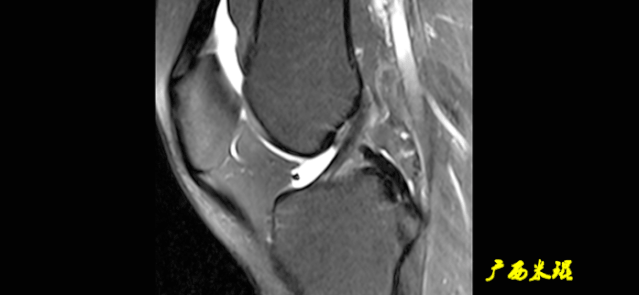

(七)ACL损伤直接征象

1)ACL本身的形态和信号异常:

2)不连续:

有韧带的低信号,但中断不连续。

一般见于新鲜损伤。

3)方向异常(ACL 下垂征):

有较完整的韧带低信号,但方向异常,呈下垂状。

一般见于股骨附着部的陈旧损伤,损伤的ACL下垂并粘附在PCL上。

4)消失:

髁间窝空虚,无韧带信号。

见于较久的损伤,损伤的ACL撕裂较重呈马尾状,无滑膜包裹,逐渐被关节内的酶腐蚀而消失。